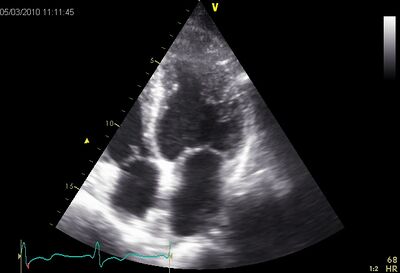

HCM01.jpg

Symmetrical hypertrophy